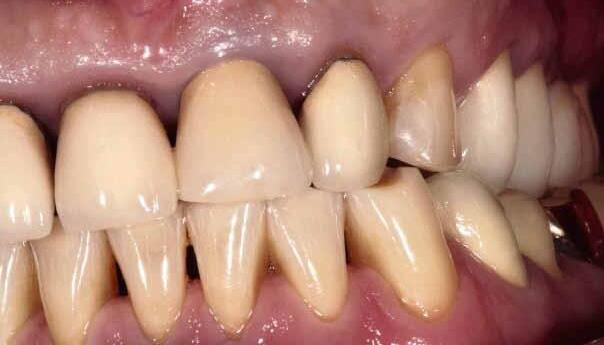

A significant number of people are unhappy with their smile, which has a considerable psychosocial impact. Although many seek cosmetic dental treatment, costs, fear and duration of total treatment are often barriers to the patients. Nevertheless, many could benefit from small and subtle changes to their teeth. With simple direct and freehand techniques, quick but significant results can be obtained that ultimately greatly improve the overall smile aesthetics.

The restoration of abfractions in the anterior area is important for aesthetic appearance especially in patients with high smile lines. Moreover, restoring abfractions strengthens the cervical area of the tooth, prevents further loss of enamel and ameliorates unpleasant sensitivity.

Black triangles and diastemas can cause entrapment of the food and accumulation of bacteria, which leads to gingivitis and ultimately periodontitis. By eliminating the black triangles and diastemas with composite bonding, the dentist not only improves the aesthetics, but also protects the long-term health of the periodontal tissues.

Worn canine cusp restoration is of special functional importance. Creating functional canine guidance with a minimally invasive composite addition to the canine cusp will protect the posterior teeth during lateral movements of the jaw. Incisal wear restorations return the youthful appearance to the smile and prevent further loss of enamel and exposure of the dentinee.

Restoring incisal wear and closing diastema with G-aenial A’CHORD. Courtesy of: Dr Aleksandra Slacan, Poland

Reshaping of teeth and diastema closure with G-aenial A’CHORD. Courtesy of: Dr Andres Silva, Spain